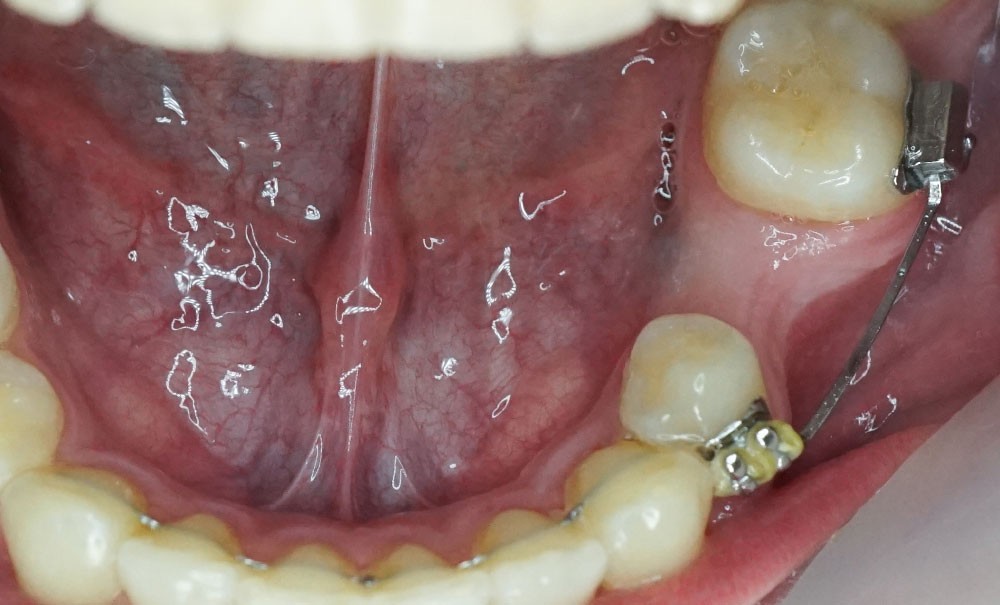

Quand un traitement orthodontique est indiqué dans le cadre de la persistance d’une molaire temporaire, l’orthodontiste doit toujours choisir entre deux solutions : maintenir ou fermer l’espace d’agénésie. Malheureusement, il est parfois confronté à une indication de maintien de l’espace d’agénésie, alors que la dent temporaire ne peut pas être maintenue jusqu’à la fin de la croissance (pour cause de caries, de réinclusion sévère, de perte, etc.) (fig. 1). La pose d’un mainteneur d’espace en fin de traitement est nécessaire, mais rien ne maintient l’os jusqu’à la fin de la croissance et la pose implantaire ! Les patients se retrouvent alors obligés de recourir à des préparations osseuses préimplantaires parfois lourdes. Le but de cet article est de proposer des solutions de maintien du volume osseux après avulsion de la deuxième molaire temporaire.